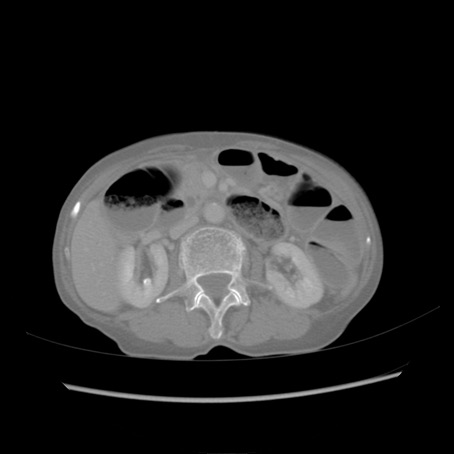

症例25(横断像)

【症例】80歳代女性

【主訴】胸のつかえ感

【現病歴】約9時間前に食後から胸のつかえた感じあり、嘔吐あり、来院。

【既往歴】胃癌(全摘)、胆摘、虫垂炎

【身体所見】心窩部に圧痛あり、反跳痛なし。

【データ】WBC 5700、CRP 0.05